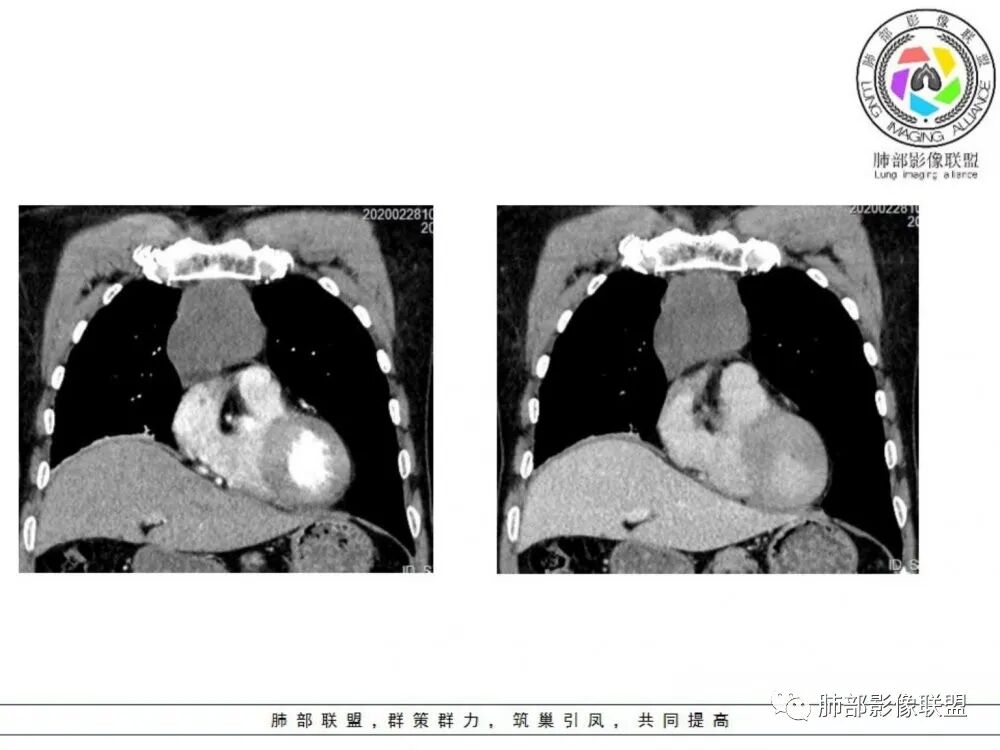

男性患者,65岁,前胸后背疼痛一个月。影像学前上纵隔分叶状的软组织肿块,肿块形态怪异,偏软,位于大血管间隙前,并有向血管后间隙发展的趋势,平扫CT值为40左右,增强扫描中心部未见强化,周围轻度的强化,约为50左右。前上纵隔的疾病谱包抬胸廓内甲状腺肿、胸腺瘤/癌、畸胎瘤、淋巴瘤。少见的心包囊肿或支气管囊肿。根据肿块的形态及强化特点,首先还是排除了胸内甲状腺肿及胸腺来源的肿物,这类的肿物强化比较明显。畸胎瘤成分比较复杂,具有软组织钙化或者脂肪类的组织,这个肿物虽然在平扫的时候好像有斑点状的钙化灶,但是总体成分还是比较单一,所以还是排除畸胎瘤的诊断。所以这样的情况是考虑:淋巴类的肿瘤,注意排除心包的囊肿或支气管来源的囊肿。

老年男性患者,前膈软组织肿块,边缘轮廓不光整,边界似乎尚清晰,内见小点状钙化灶,平扫密度欠均匀,增强后轻度强化表现,边缘有些斑片状的高强化区。综合考虑胸腺瘤或胸腺鳞癌,神经内分泌癌强化弱了一些。患者年龄较大,生殖细胞肿瘤不考虑,淋巴瘤血管包绕不够,可能性不大

老年男性,前胸后背痛一个月,前纵隔不规则肿块,分叶,向纵隔血管间隙进入,且与纵隔血管分界不清,增强边缘轻度强化,中间可见无强化区,似见点状钙化,PET为高代谢,考虑为来源于胸腺,胸腺瘤或胸腺鳞癌可能

临床,老年男性,病史一月。1 定位,骑跨大血管,大部分位于胸腺区域内,周边部分胸腺脂肪有混浑浊,起源于胸腺区的组织应该没有问题。2 定性 。恶性征像,分叶,大血管侵润,pet高代谢,左侧庄层胸膜增厚(类似脑膜瘤的脑膜尾征,良性表现?)。良性征像,病灶均匀,无明确坏死?综合恶性征像多些,考虑恶性可能大。病灶分两部分,部分层面似有明确分割,两个性质的病灶长一块,还是,一个病灶两种不同成分?一个病灶伴均匀坏死?CT值41hu,坏死好像高了点,一个病灶,相同成分,只是血管分布不同,增强是持续流入型强化。纤维类?编不下去了,岔路太多,祭出法宝按概率蒙吧:侵袭性胸腺瘤>神经纤维瘤>乏血供CD

中老年男性,前纵隔占位,基本居中,向两侧生长;边缘膨隆分叶,部分边界不清,增强不均匀轻中度强化,坏死区边界不清;周围多发增大淋巴结,考虑恶性。主要在胸腺癌、胸腺瘤、淋巴瘤之间鉴别。病灶偏软,有钻缝样生长,这些征象偏向于淋巴瘤。但此例老年患者,病灶内有点状钙化,缺乏结节堆砌感,倾向胸腺癌诊断。